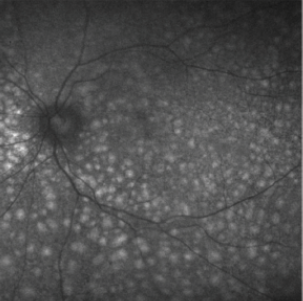

Figure 2. FAF demonstrates leopard spots.

Fluorescein angiography in UES typically shows areas of hypofluorescence corresponding to leopard-spot pigmentation, with angiographic leakage rarely identified.2,4 In the acute setting, the leopard spots will appear as hyperfluorescent on fundus autofluorescence (FAF), but over time this may change to a mix of hyper- and hypoautofluorescence on FAF (Figure 2). Corresponding OCT through the spots will reveal focal thickening of the RPE. Both of these findings may diminish with resolution of subretinal fluid, but typically the FAF changes will persist.16